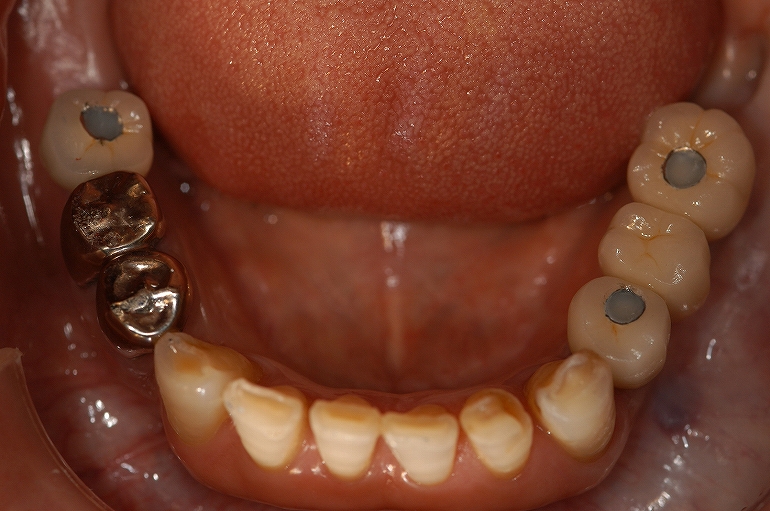

Before

(治療前)下顎。

After

(治療後)下顎。

インプラントと審美修復。